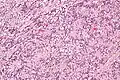

IPMs are diagnosed by examination of the tissue by a pathologist. They have a rim of peripheral lymphoid tissue (remnant of a lymph node) and consist of spindle cells with nuclear palisading. Red blood cell extravasation is common and blood vessels surrounded by collagen with (fine) peripheral spokes (amianthoid fibers) are usually seen.[2]

Immunostains for smooth muscle actin and cyclin D1 are characteristically positive. The main histologic differential diagnosis is schwannoma.